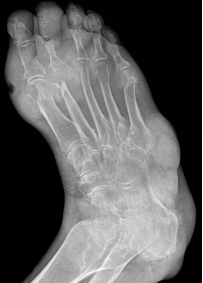

足骨

包括跗骨、跖骨和趾骨。跗骨共7块,分前、中、后列。后列包括距骨和跟骨;中列为距骨前方的足舟骨;前列为内侧楔骨、中间楔骨、外侧楔骨及跟骨前方的骰骨

跖骨,共5块,近端为底,与跗骨相接;中间为体,远端称头,与近节趾骨底相接

趾骨,共14块,踇趾为2节,其余各趾为3节。分为近节趾骨,中节趾骨和远节趾骨。每节趾骨近端为底,中间部为体,远端为滑车